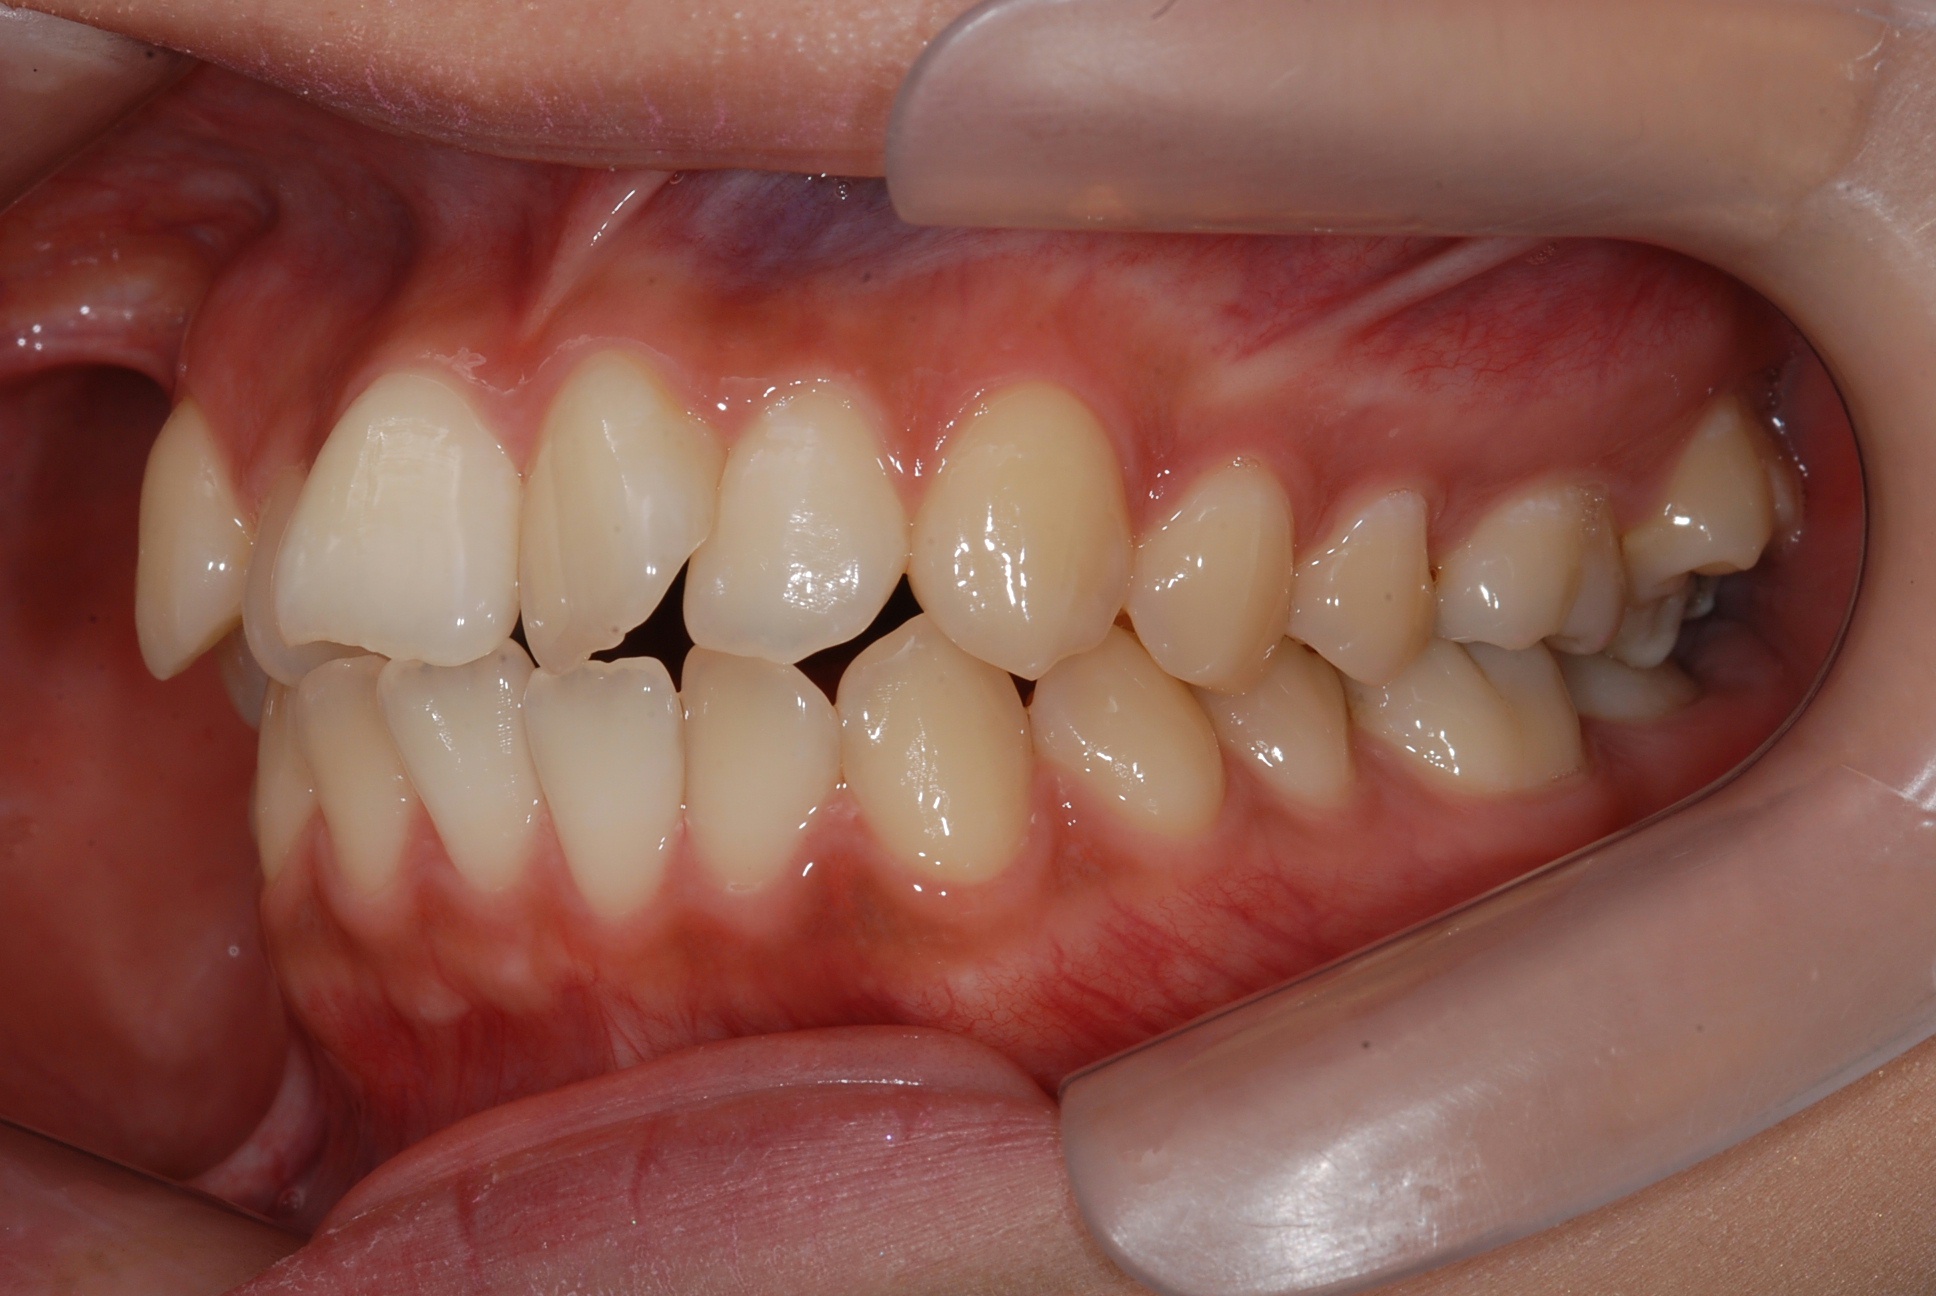

치료 후 사진입니다.